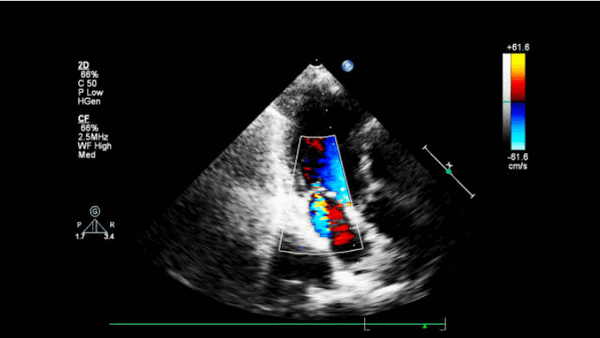

- Острая МН. Это может быть связано с дисфункцией или разрывом сосочковых мышц или разрывом хорды, что может быть определено с помощью 2-D эхокардиографии. Там может быть надрыв сосочковой мышцы или хорды, а струю митральной недостаточности можно увидеть на непрерывном волновом или цветном доплеровском картировании потока.

На 2-е и 20-е сутки заболевания с помощью ЭхоКГ определяли количественные показатели ИМР [площадь регургитационного отверстия (SRO мм2), регургитационный объем (RV, мл), фракция регургитации (RF, %)] с использованием комбинации цветового допплеровского картирования проксимального сходящегося потока регургитации (PISA-метод, proximal isovelocity surface area method) и количественной допплер-ЭхоКГ (Q-DE-метод) [1—3].

У всех больных для оценки показателей деформации МК измеряли величину систолического верхушечного прогиба створок МК — расстояние между точкой смыкания створок и плоскостью митрального кольца (h, см) (рис. 1).

митральная регургитация на ЭхоКГ